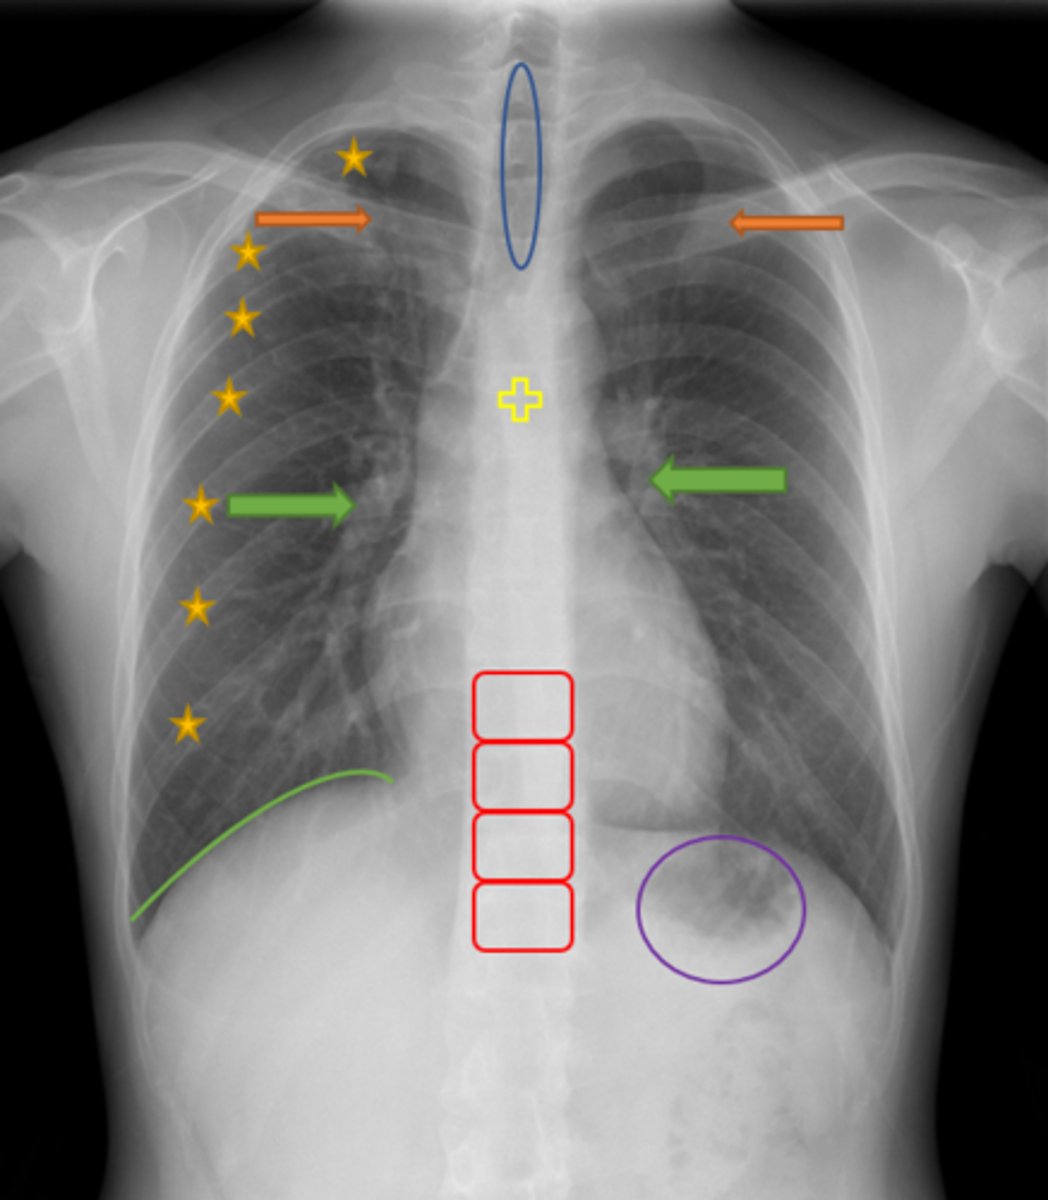

Aortic knob/arch

Pink Arrow

Left ventricle and border of the heart

Purple Line

Pulmonary arteries

Blue Arrows

Normal film

Interpretation

Trachea

Blue Oval

Pulmonary arteries

Green Arrows

Vertebrae/spine

Red Blocks

Clavicle

Orange Arrows

Ribs

Yellow Stars

Diaphragm

Green Line

Gastric bubble/stomach

Purple Circle

Carina

Yellow Cross